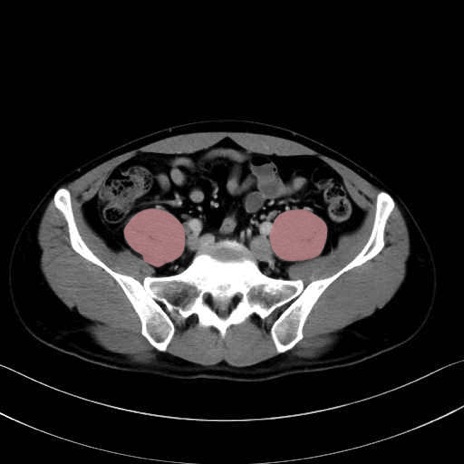

2. 腸腰筋群と骨盤底筋

大腰筋 (Psoas major)

腸骨筋 (Iliacus)